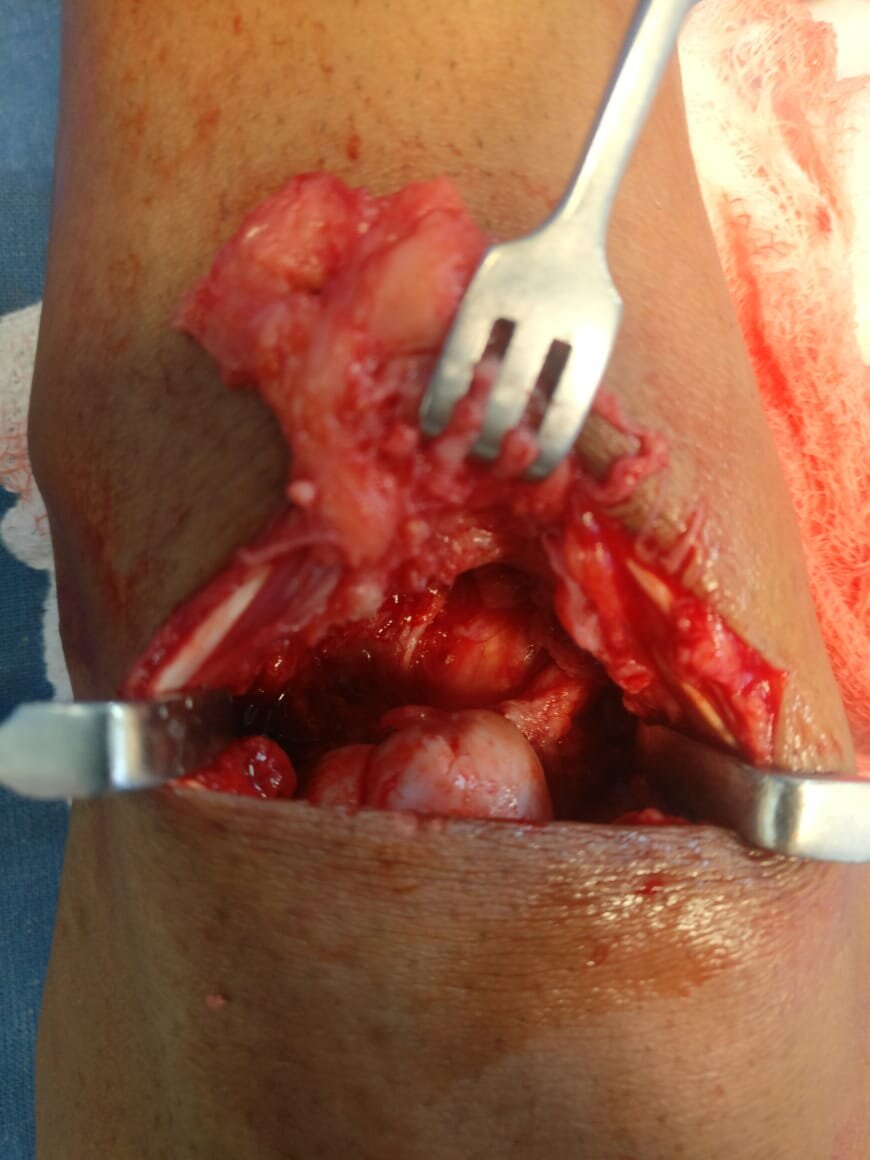

GCT of Flexor tendon sheath befoe and after excision